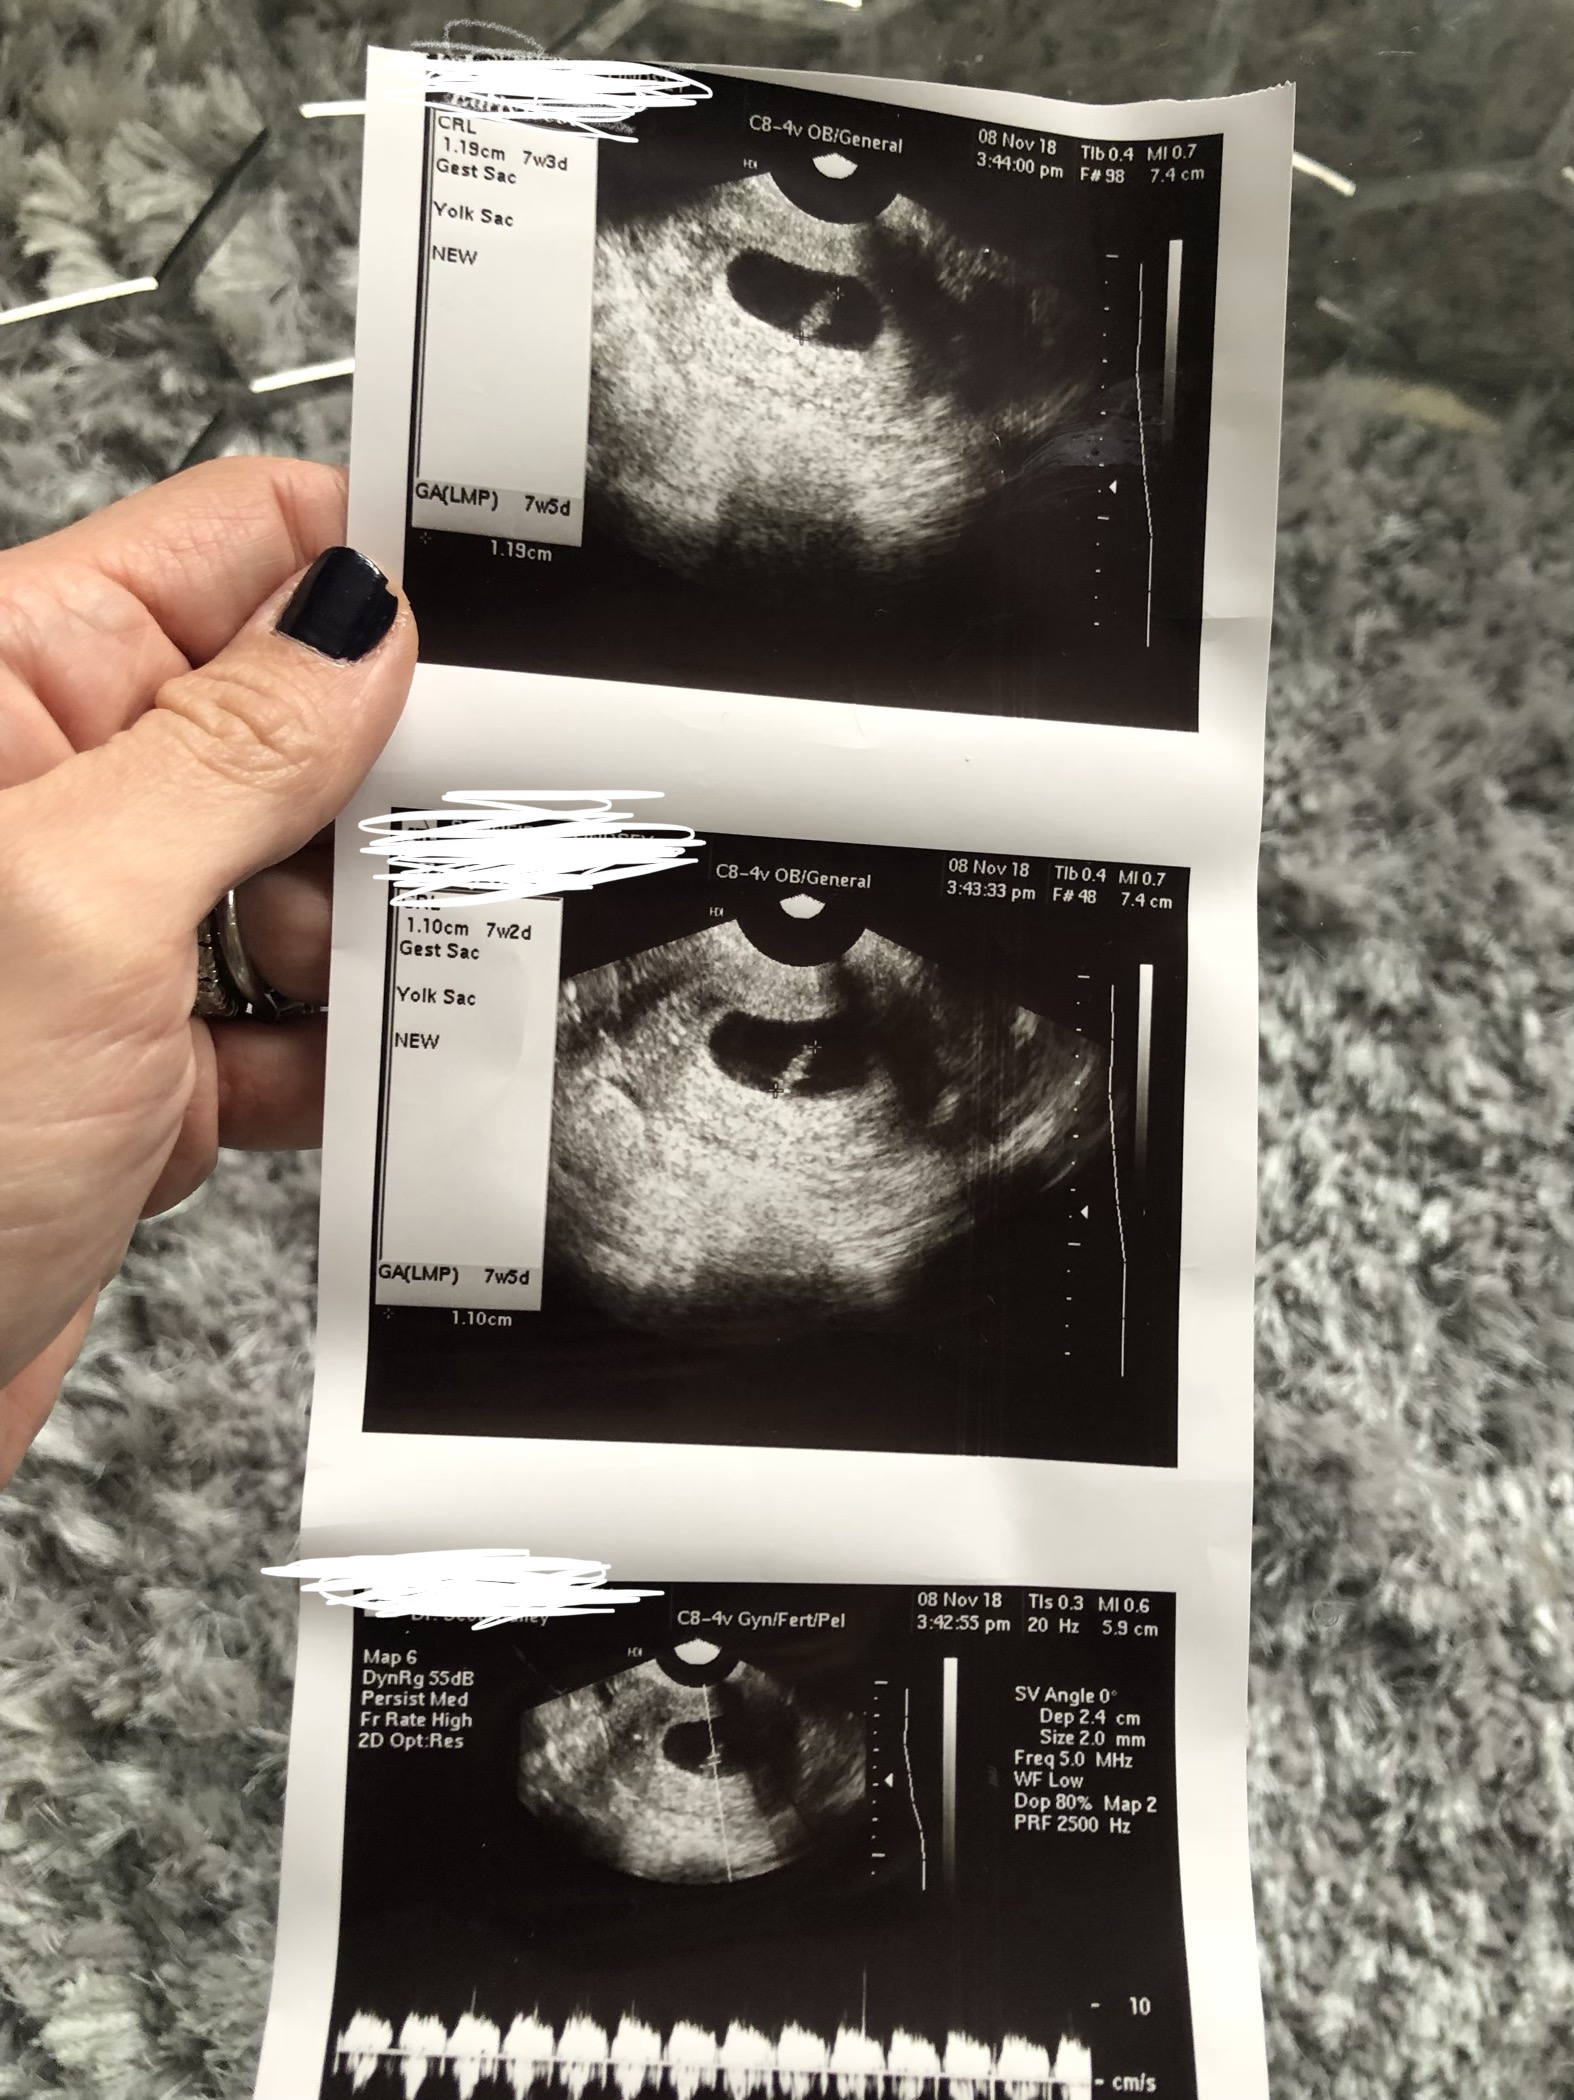

7 week vaginal ultra sound. Any guesses greatly appreciated

Ramzi isnt accurate but they say left girl right boy your little one is right in the middle haha! ( vaginal scan flip it )